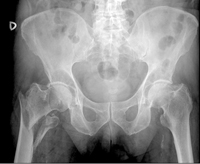

L'osteoporosi és una malaltia caracteritzada per una disminució de la massa òssia i una alteració de l'arquitectura de l'esquelet que comporta fragilitat i susceptibilitat per a les fractures (Figura 1). La fractura de maluc (Figura 2) és la de major gravetat entre totes las fractures que poden aparèixer i és un problema major de salut per la mortalitat, principalment en el primer any després de la fractura, i per la discapacitat que pot ocasionar. L'osteoporosi en els ancians és secundaria a diversos mecanismes, entre els quals destaquen els relacionats amb el calci i la vitamina D, i aquest dèficit vitamínic s'ha mostrat sobretot en els que estan institucionalitzats, i en els que presenten fractura de maluc. Tot i que l'associació fractura de maluc-dèficit de vitamina D és coneguda, està poc estudiada en el nostre medi i són desconeguts els possibles factors afavoridors d'aquest dèficit de vitamina D.

En aquest estudi es van incloure els 324 individus majors de 65 anys que ingressaren en l'hospital durant un any, per una fractura osteoporòtica de maluc, és a dir, la que es presenta després d'un traumatisme de baix impacte, com una caiguda a terra. Tenien una edat mitja de 83 anys i el 80% eren dones. En tots els pacients es van practicar anàlisis per determinar els nivells sanguinis de vitamina D i l'estat nutricional. També es realitzaren qüestionaris per conèixer la capacitat funcional abans de la fractura i el grau d’exposició solar durant els últims tres mesos. Els qüestionaris de capacitat funcional valoren si existeix independència o no per desenvolupar funcions bàsiques como caminar, pujar escales, aixecar-se del llit o d'un silló, alimentar-se o vestir-se. El grau d'exposició solar es va valorar a través d'un qüestionari que considera exposició solar nul·la els pacients reclosos a domicili, exposició solar pobre o mitja segons el número de dies de sortida a la setmana al carrer i exposició solar activa quan es realitza exposició expressa al sol.